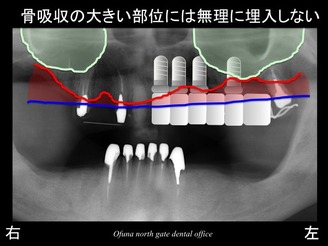

いつものように 骨吸収の状態を分かりやすくするために

骨吸収の状態を線で書いたのが以下のレントゲンになります。

青線が骨吸収を起こす前の骨の位置です。

赤線は、現在の骨の位置です。

さらに分かりやすくするために 骨吸収部位を赤色の領域で表します。

奥歯では、骨吸収が大きいのがわかるかと思います。